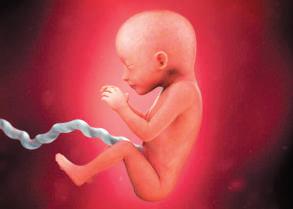

розмір

ся кістковою. За

допомогою якісної

ультразвукової діа-

гностики плода в

Рис. 42.9.